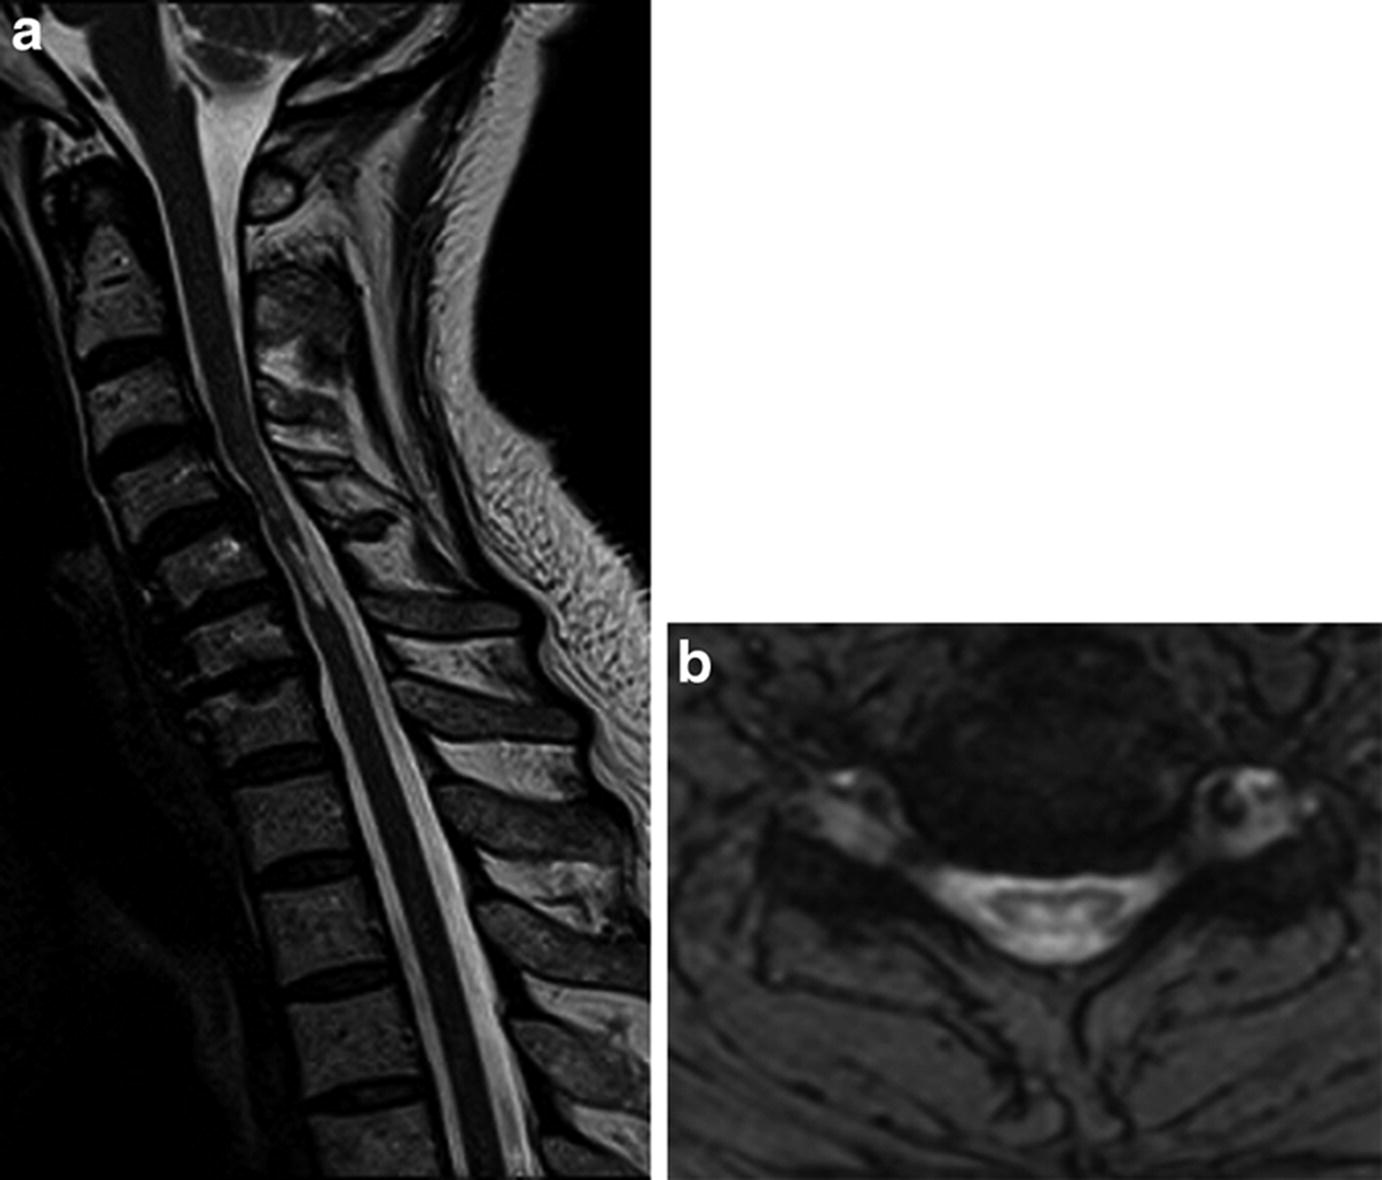

Transverse Myelitis In A Child With Covid 19 Pediatric Neurology

Transverse Myelitis In A Child With Covid 19 Pediatric Neurology from els-jbs-prod-cdn.jbs.elsevierhealth.com

The spinal cord also carries sensory information back to the brain. However ms can look like anything and may uncommonly involve the whole transverse diameter or only the anterior part. An mri can show inflammation of the spinal cord and other potential causes of the symptoms, including abnormalities affecting the spinal cord or blood vessels.; Myelitis, is a collective term simply referring to any inflammation of the spinal cord. Ischemia as a result of arterial infarction is typically located in the anterior parts, but may involve the entire transverse diameter. A case of transverse myelitis following catheterization of the right fifth intercostal artery is reported here to emphasize the fact that bronchial arteriography does carry some hazard which must be assessed in the light of the presenting clinical problem. Diffusion tensor imaging in idiopathic acute transverse myelitis. Able to rule out any secondary complications from a.